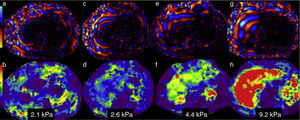

Image analysis and liver stiffness measurementWavelength mapWavelength analysis can be done statically in a fixed image or in a video showing the wavelength motion. It verifies that the wavelengths sent by the passive driver penetrated the liver tissue and were adequately distributed. Wavelengths are thin and parallel in the normal liver (Figure 3a). As the grade of fibrosis increases, the wavelengths become thicker and faster (figures 3c, 3e, and 3 g).

Information analysis. The wavelength map in 4 patients with different grades of stiffness is in the upper row. The lower row corresponds to the elastographic or color map of each of them. Figures a, c, e, and g show the increase in thickness and the irregularity of the wavelengths as the grades of fibrosis increase. The elastographic maps show the changes in color of the liver and their respective stiffness measurements: b) purples for 2.1kPa=F 1; d) greens and blues for 2.6kPa=F2; f) greens and yellows for 4.4kPa=F3; and h) red for 9.2kPa=F4. Compare the colors of the liver with the color bar on the left side.

This color map makes it possible to make a rapid visual evaluation of normality or abnormality of liver parenchymal stiffness. To make this assessment, the colors of the liver are compared with the colorimetric scale accompanying each image. This affords a first appreciation of the grade of fibrosis as absent, incipient, moderate, or intense (figures 3b, d, f, and h).

In our equipment, blue and purple tones are located at the lower end of the scale and correspond to minimum stiffness. Red is at the upper end of the scale and represents maximum stiffness, whereas yellow and orange tones correspond to intermediate stiffness values. The color map provides a visual appreciation of whether the fibrosis distribution is homogeneous or heterogeneous.16

Automatic quantification programs have recently been developed that need no human intervention. Given that the elastographic map covers the entire circumference of the abdomen, it also makes it possible to recognize whether there is an increase in spleen stiffness in the same image (Figure 3 h).